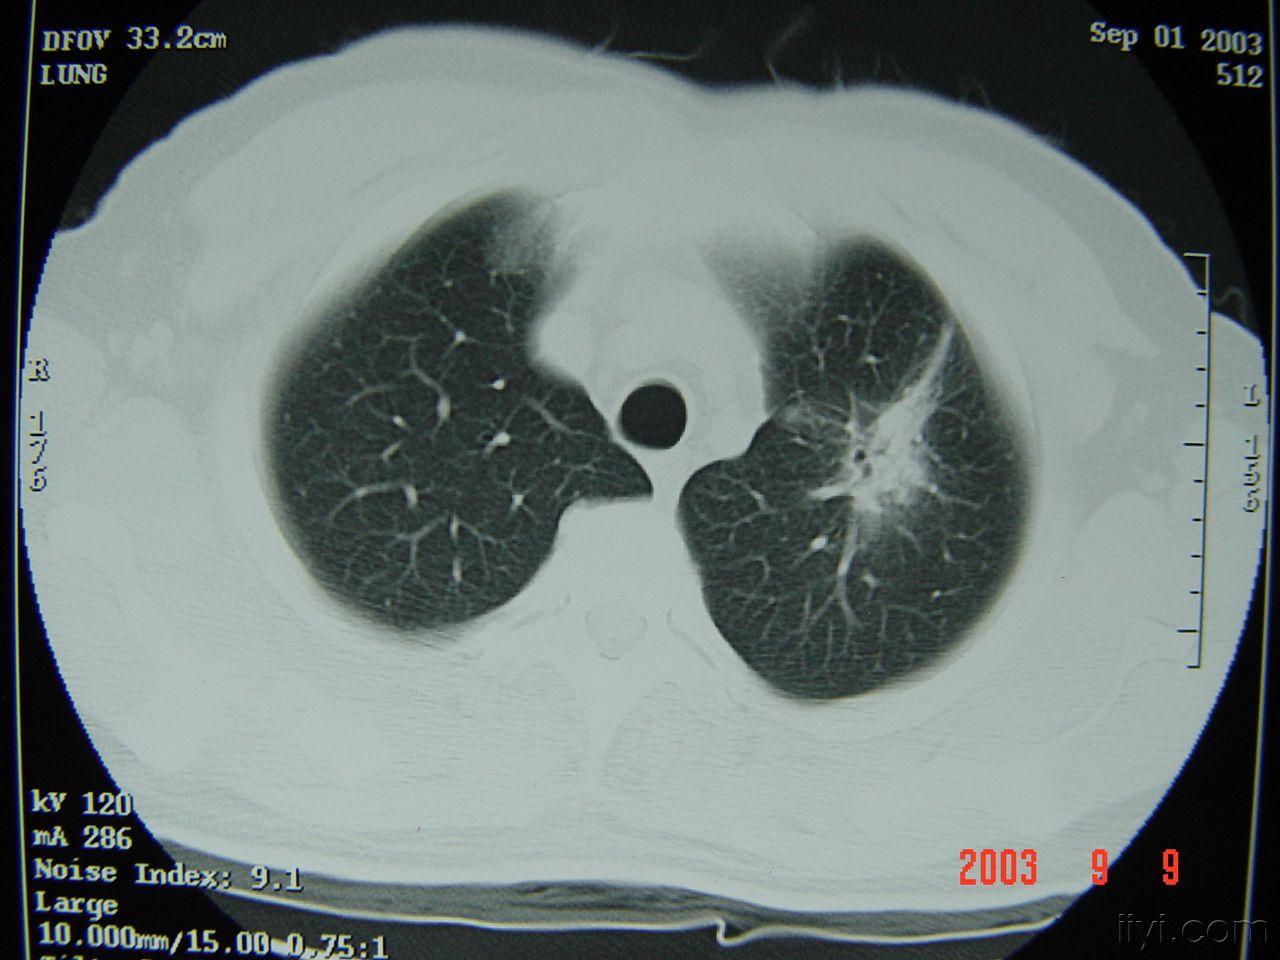

肺癌- 医学影像学讨论版 - 爱爱医医学论坛

图片尺寸2048x1536